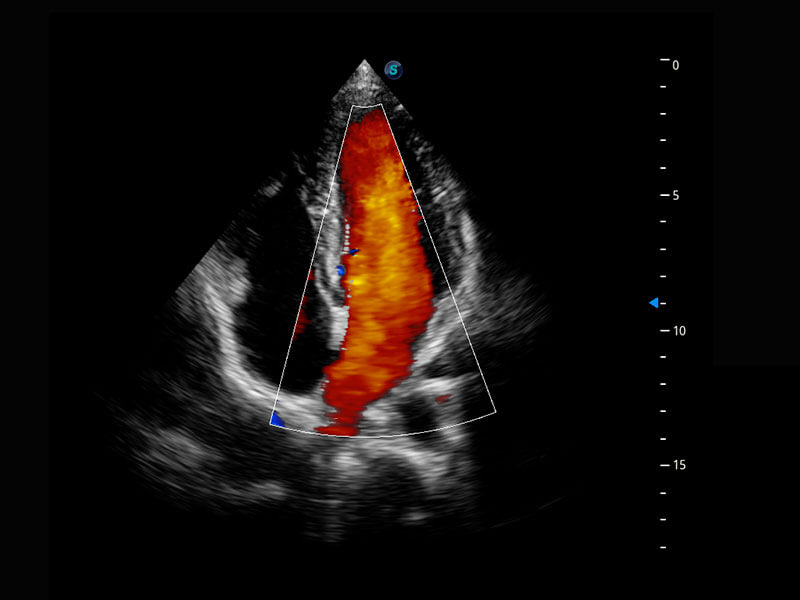

胎心筛查

P60搭载一系列胎儿心脏成像技术,实现更精细的胎儿心脏评估。

• 四腔切面

• 四腔心血流